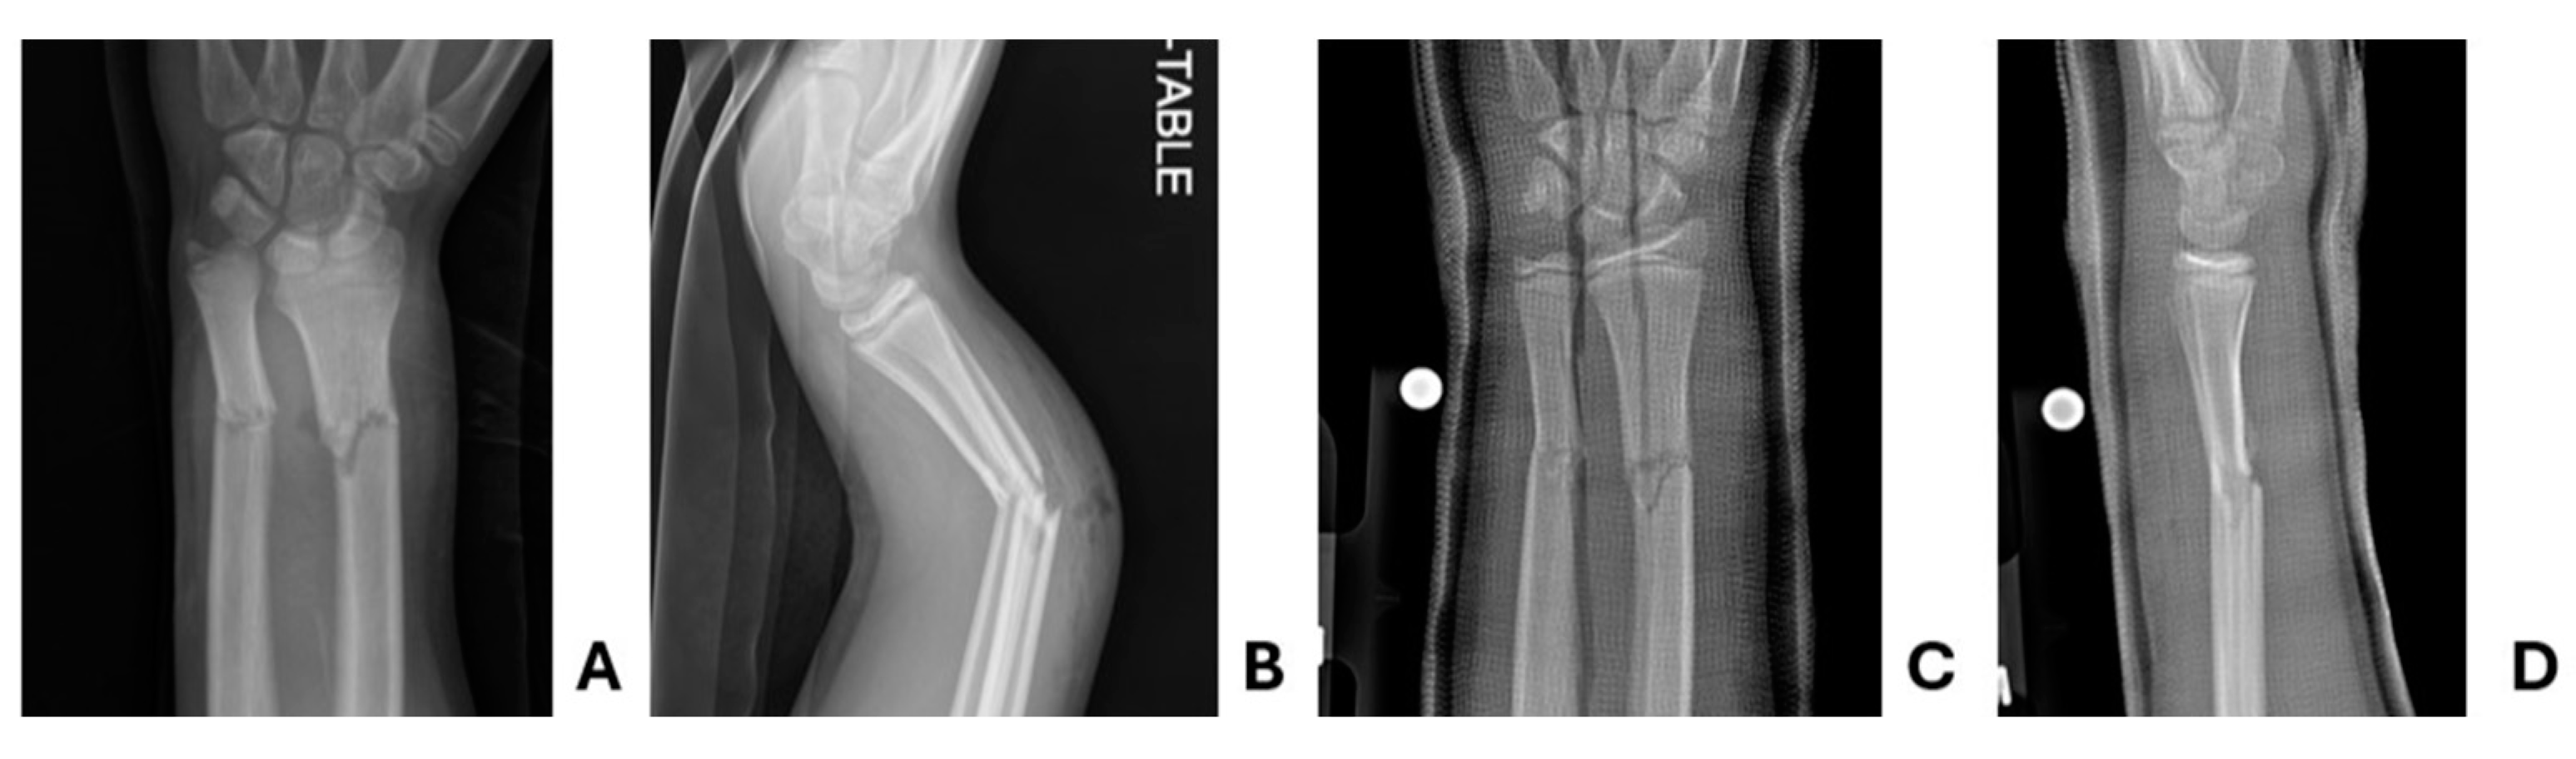

Figure 5. Patient two pre- and post-reduction radiographs. Pre-reduction A anteroposterior and B lateral radiographs demonstrating acute distal radius and ulna fracture. Same day post-reduction C anteroposterior and D lateral radiographs demonstrate stable interval reduction.

12-year-old male presented to the ED with an obvious deformity of the left arm following a dirt bike crash. Past medical history was notable for a Salter Harris type two distal radius fracture treated with casting one year prior. The patient was operating a dirt bike at speeds of approximately 15 miles per hour when he lost control. The patient was helmeted and there was no loss of consciousness. Immediately following the crash, the patient was found to have an obvious deformity of the left arm, reporting 9/10 pain in the extremity. Intravenous access was obtained by EMS and he was initially provided 50 mcg fentanyl before a splint was applied and his arm was rested on a pillow. In the pre-hospital setting, the patient was provided two additional doses of 25 mcg of fentanyl, over 30 minutes.

Upon arrival to the ED, he was hemodynamically stable. Examination was notable for deformity of the left forearm with a 1-2 mm open wound overlying the site. Distal perfusion, motor function, and sensation were intact. There was no concern for other injury about the remainder of his body. X-rays of the left radius and ulna were obtained and notable for an apex dorsal angulated radius and ulna diaphysis fractures (Figure 5). Pediatric Orthopedics was consulted and recommended irrigation and closed reduction. In the ED, he was provided another two doses of 50 mcg of fentanyl, for a total of 200 mcg over 90 minutes. In light of his analgesia requirements, it was decided to facilitate the procedure with a supraclavicular block. This was performed without complications. He subsequently underwent irrigation of the puncture site before a bivalved long arm cast was placed. Post-reduction x-rays confirmed adequate length, alignment, and rotation. No further analgesic doses were required during his ED stay. X-rays obtained during follow-up 1, 3, and 6 weeks later demonstrated stable alignment of the fracture site. He was not felt to need any further follow-up and was cleared from this injury.